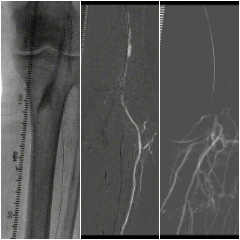

★ 手术过程

图:术中

★ 手术结果

图:手术结果